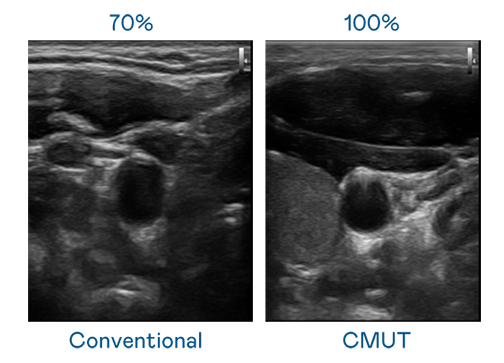

CMUT 技术是一种用电容式微机电元件来产生超音波讯号的技术。与传统 PZT 压电式技术相比,CMUT 频宽增加 30%,更宽频的超音波讯号让影像解析度大幅提升,是实现高影像品质医疗超音波扫描、促进精准医疗发展的关键技术。

超音波影像的解析度高低,首先取决于探头能发出的讯号频宽。爱游戏体育网页登录 CMUT 可提供高清晰的超音波讯号,提供高频宽、高灵敏度、影像纹理细节更高的超音波影像,协助医护人员缩短影像判读时间及利用精准的医疗影像进行诊断。